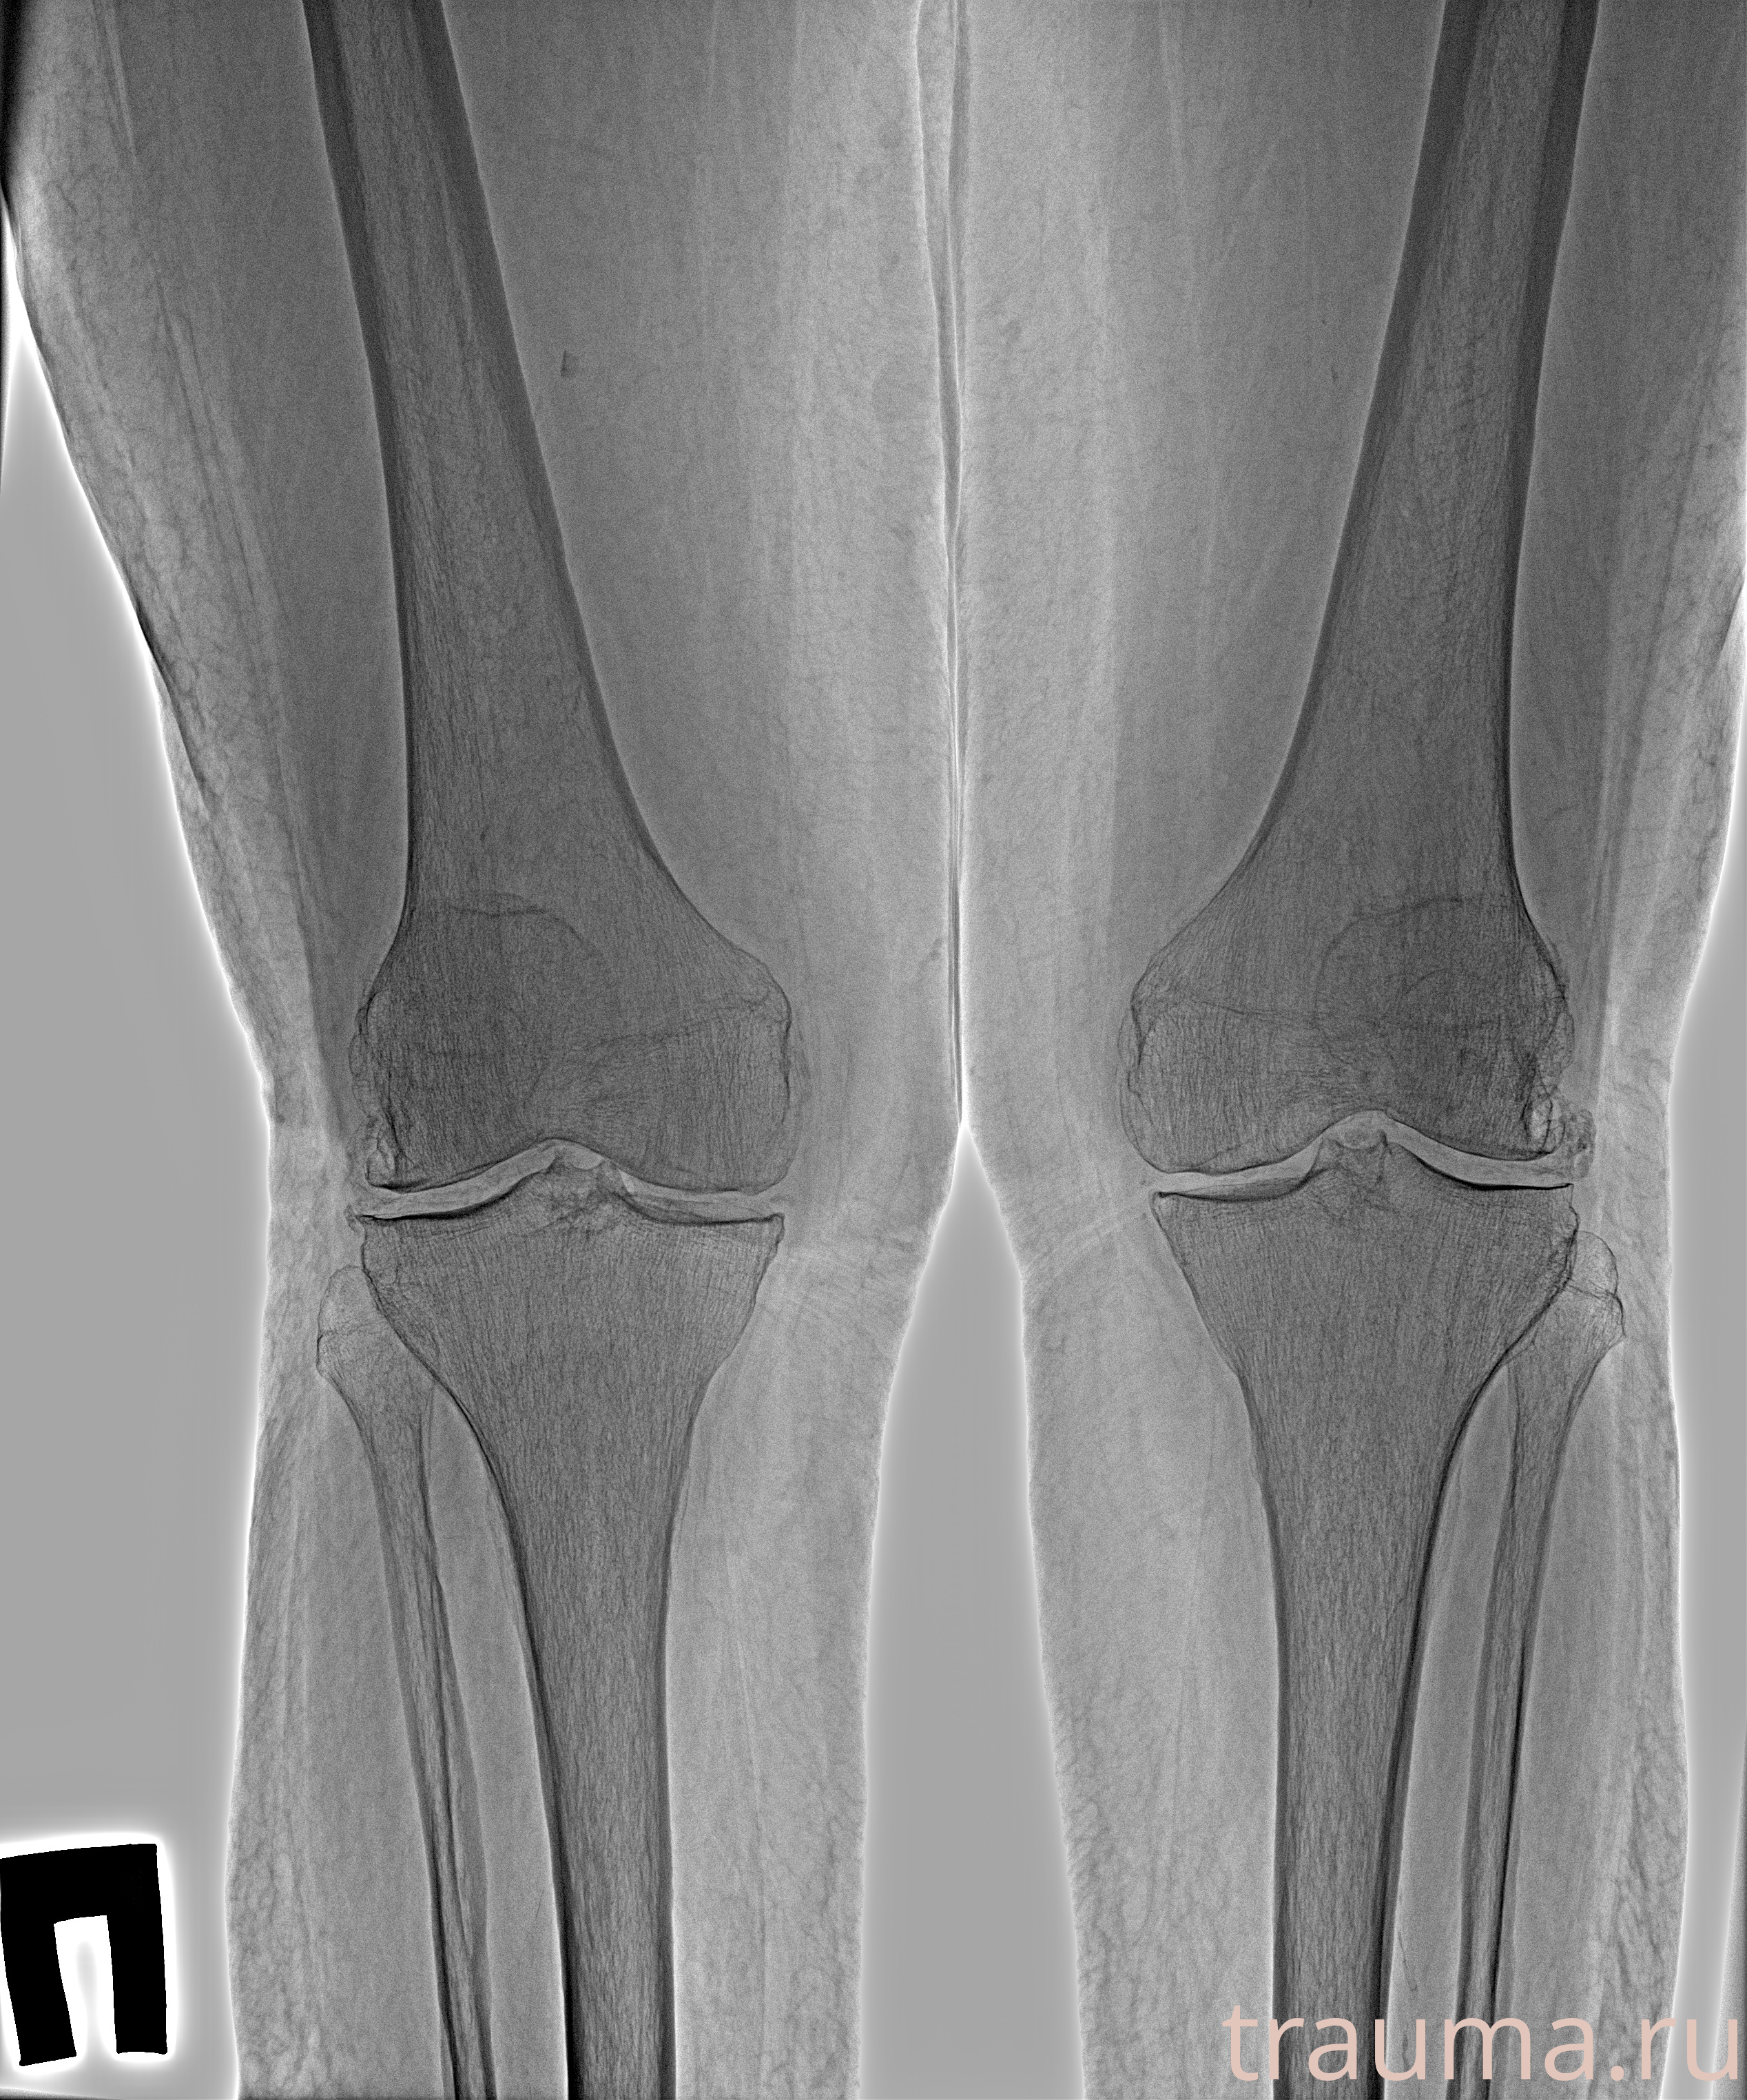

Рентгенограммы

Рентген на дому: по вашему адресу приезжает врач-рентгенолог, травматолог-ортопед с мобильным рентгеновским аппаратом, проводит диагностику травмы или заболевания, делает необходимые рентгенограммы, дает рекомендации по дальнейшему лечению. Получить качественные снимки в домашних условиях возможно благодаря уникальной методике, разработанной МосРентген Центром для института  Склифосовского